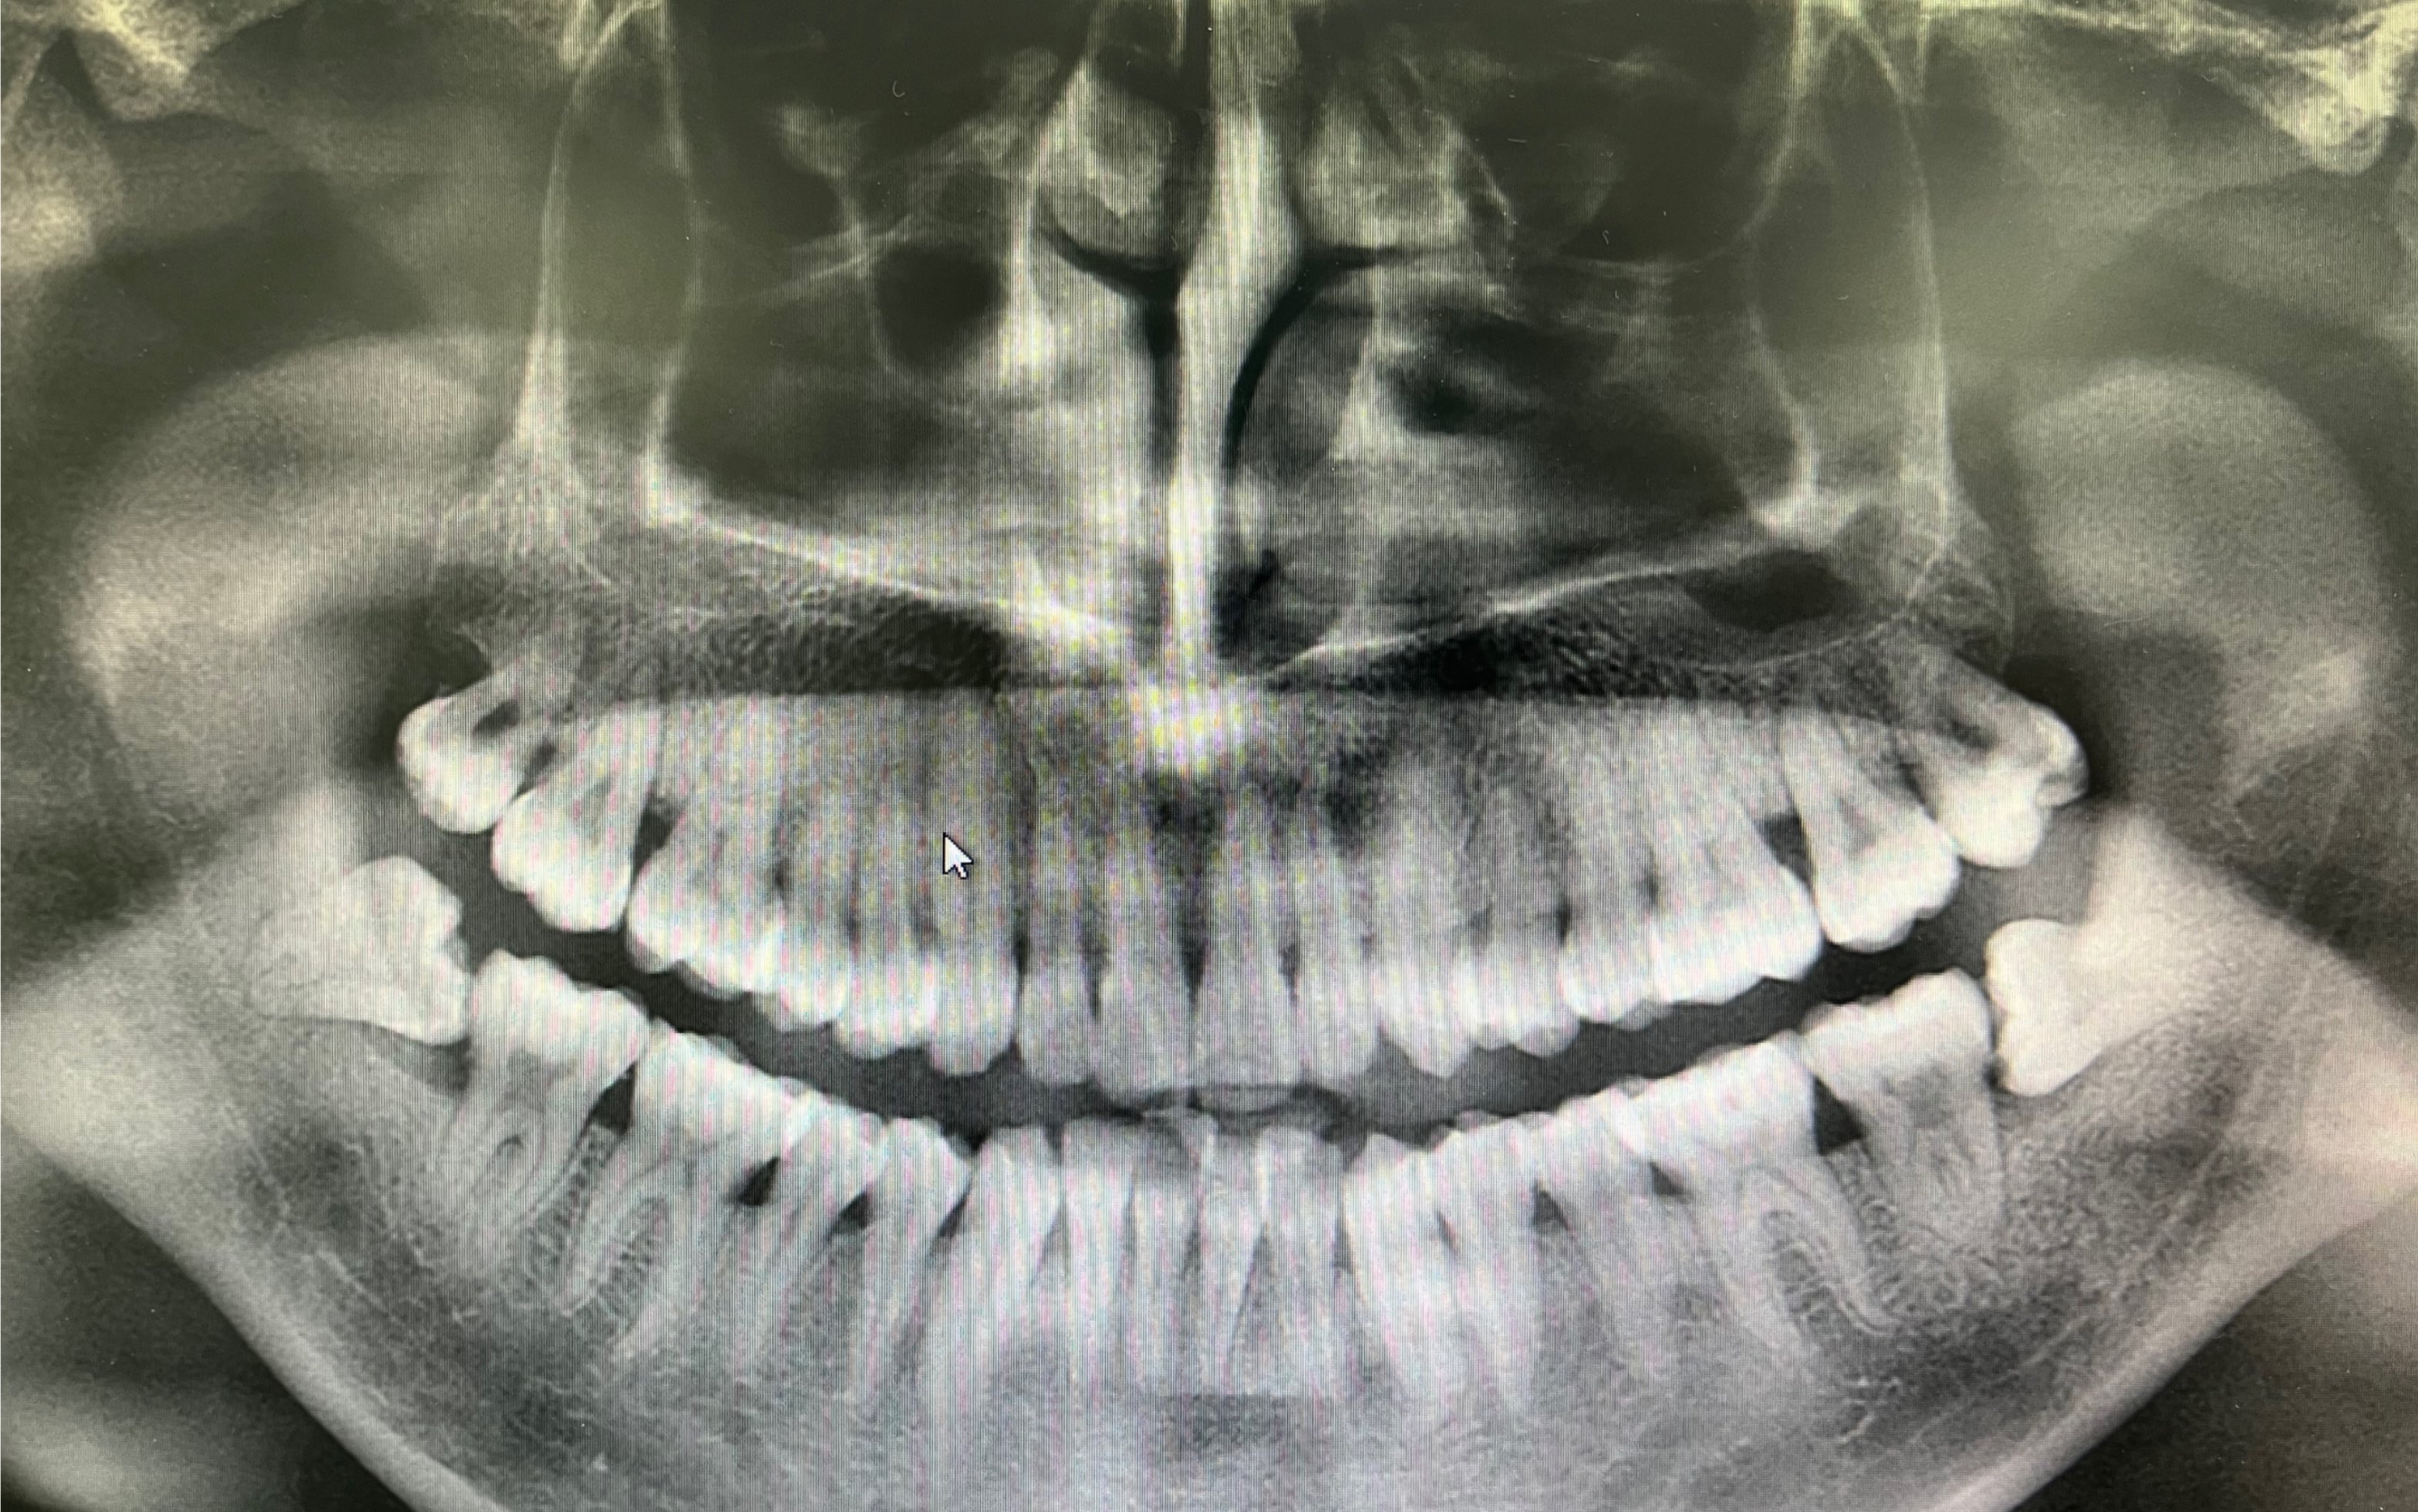

【优秀病例分享】下颌近中中位智齿拔牙病例